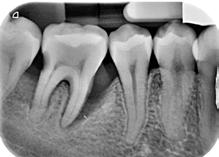

Lâexamen exobuccal Ă©tait sans particularitĂ©s. Lâexamen endobuccal a objectivĂ© une inflammation marginale modĂ©rĂ©e Ă sĂ©vĂšre gĂ©nĂ©ralisĂ©e avec un indice dâOleary Ă 68%, un indice gingival (BoP = Bleeding on Probing) Ă 76%, et un trama occlusal sur 42 (Figure 1). Le bilan parodontal montre des sites avec une profondeur de sondage (PS) de 12mm, et plus de 50% des dents prĂ©sentant une perte dâattache â„ 5mm. Le bilan radiographique a montrĂ© des pertes osseuses terminales, avec un rapport perte osseuse/Ăąge Ă 4,5 (Figure 1)

AprĂšs 6 mois, pas de profondeurs de poches â„ 6mm, avec un indice de plaque Ă 9% et un indice gingival < 10%. La thĂ©rapeutique non chirurgicale a permis un gain dâattache

stable qui sâest traduit par une diminution des profondeurs de sondage en regard de la 11, 21, et 36 dont le pronostic Ă©tait dĂ©favorable, mais aussi lâapparition dâimportantes rĂ©cessions postthĂ©rapeutique (Figure 4). La chirurgie avec lambeau dâaccĂšs a permis Ă©galement dâamĂ©liorer le niveau osseux de la 46. Le pronostic gĂ©nĂ©ral Ă long terme de la patiente a Ă©tĂ© amĂ©liorĂ©.

La réévaluation Ă 3 mois a montrĂ© une amĂ©lioration de lâĂ©tat parodontal avec plus de 90% de sites prĂ©sentant des PS †4mm (3). LâefficacitĂ© du dĂ©bridement mĂ©canique non chirurgical associĂ© Ă un bon contrĂŽle de plaque individuel dans le traitement des parodontites sĂ©vĂšres a Ă©tĂ© largement documentĂ©e dans plusieurs revues systĂ©matiques (6). Toutefois, la prĂ©sence dâune poche rĂ©siduelle de 6mm avec saignement au sondage sur la 46 reprĂ©sentait un rĂ©sultat incomplet et a nĂ©cessitĂ© dans notre cas un traitement chirurgical par lambeau dâaccĂšs afin dâĂ©viter la progression de la maladie (7).

Figure 4 : (a) Vue clinique Ă 6 mois ; (b) bilan radiographique Ă 3mois (b) ; (c) Retro alvĂ©olaire sur la 46 avant et aprĂšs lambeau dâassainissement